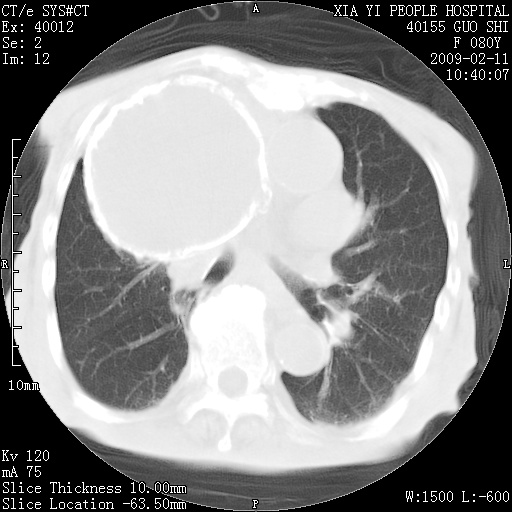

以下是引用随光逐影在2009-2-16 16:34:00的发言:[br]1)考虑右前纵隔皮样囊肿。2)双侧少量胸腔积液。

以下是引用zjzjr在2009-2-16 17:30:00的发言:[br]支持囊性畸胎瘤 双侧少量胸腔积液。